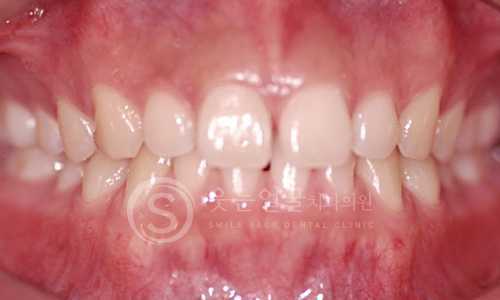

한눈에 보는

임플란트 전후사진